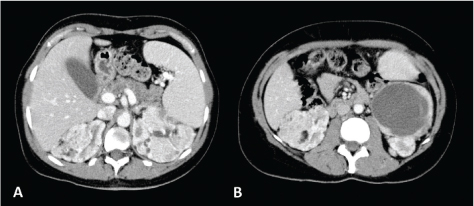

Fig 3

Figure 3. Unenhanced CT axial scan of the abdomen (A and C) and CT of the abdomen during arterious phase (B and D) of a 53-year-old woman showing the presence of classic AMLs, recognizable by the adipose component of the lesion.